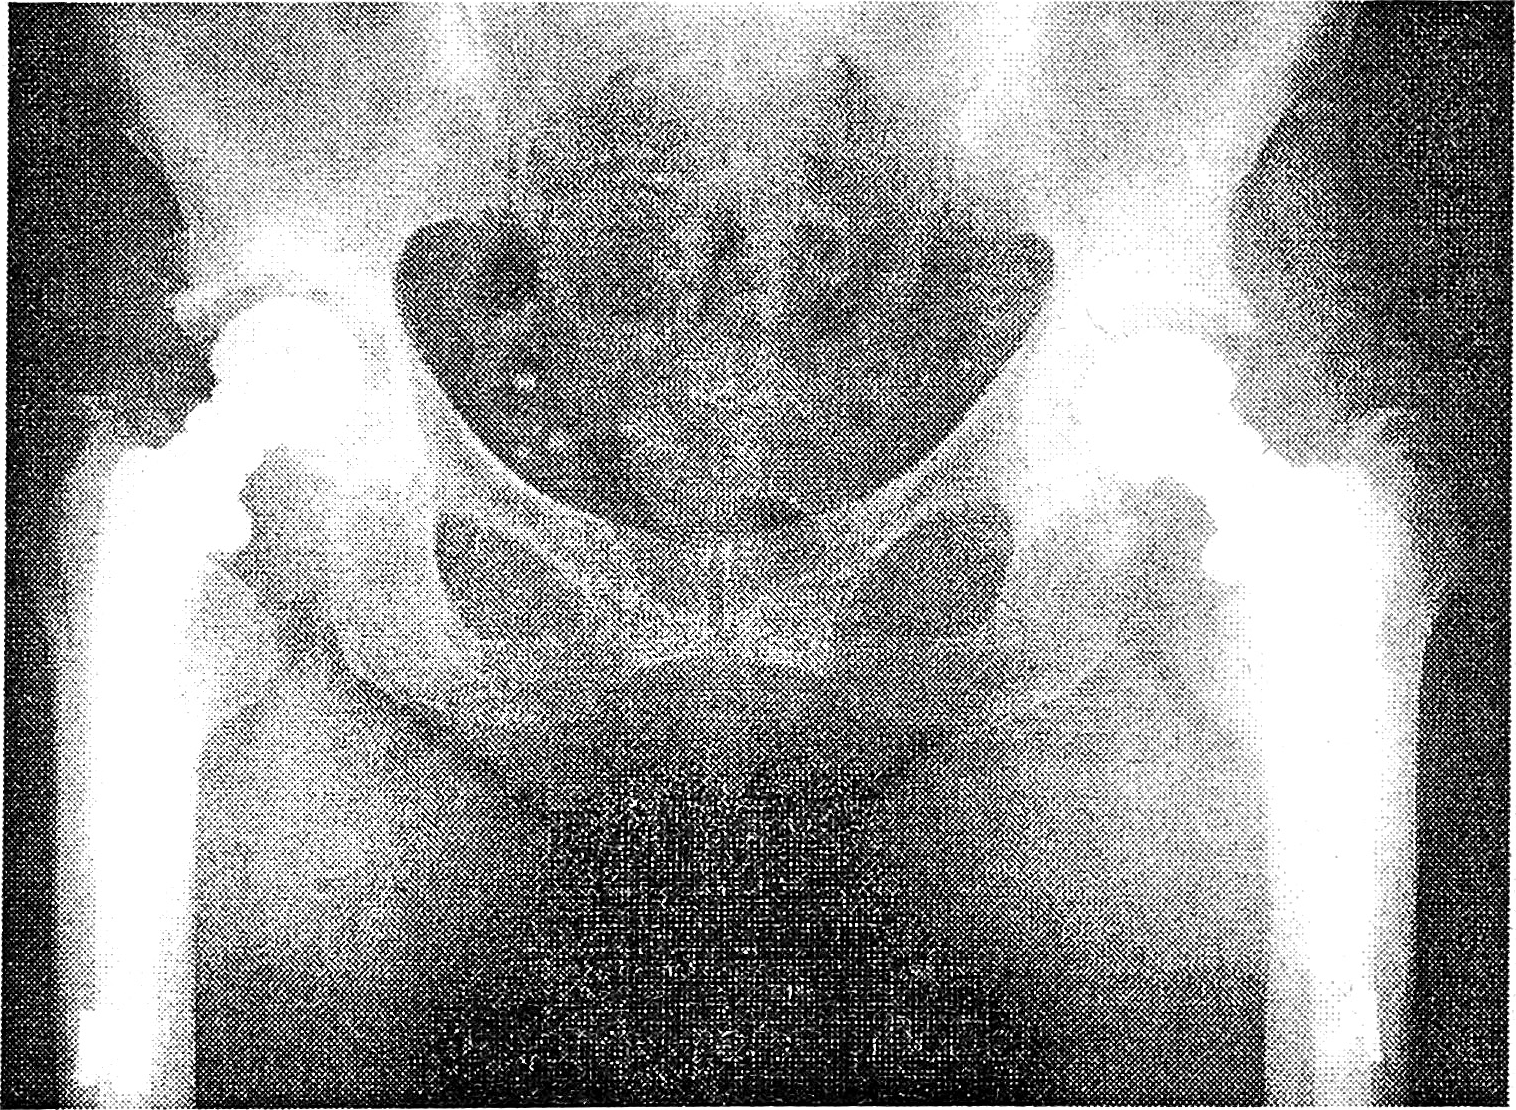

Рис. 2. Двустороннее эндопротезирование протезом Мовшовича—Гаврюшенко.

Заканчивают установку протеза монтажом шейки и головки, причем если ножка установлена правильно, применяют прямую шейку, а если необходимо создать варус, вальгус или ротационную девиацию, используют углообразную шейку. Отверстие на головке должно располагаться в ее нижнем (ненагружаемом) сегменте. После вправления головки рану послойно ушивают с установкой 2—3 катетеров для активной эвакуации гематомы в течение 48 ч (рис. 2).